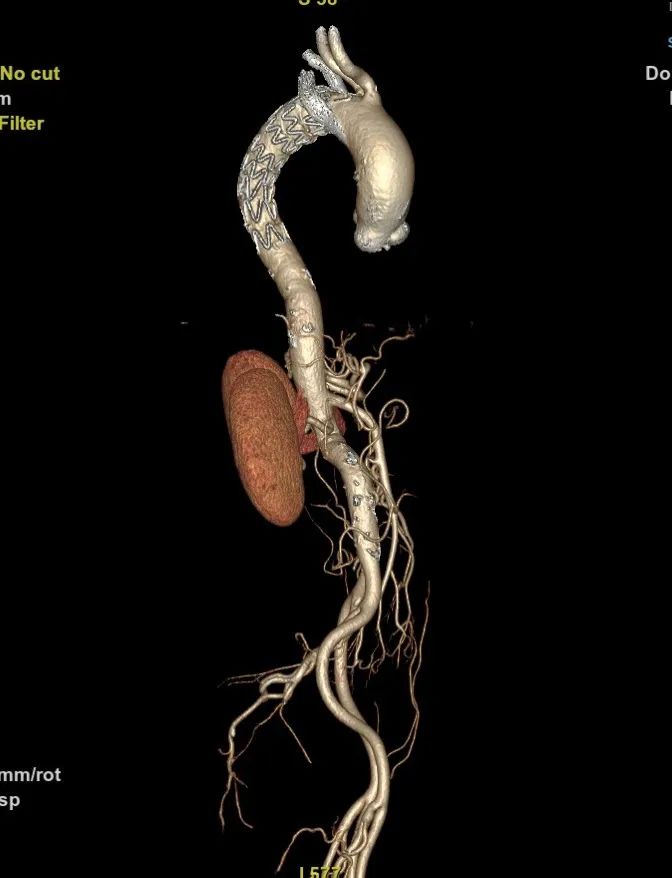

术后随访:

6个月后再次随访,CTA影像图显示血管形态良好,血管支架通畅。